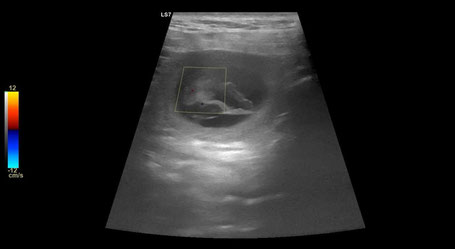

Ultraschall

Heute hatten wir mit Sky den Ultrashall-Termin beim Tierarzt zur Sicherung der Trächtigkeit. Da wir schon einige Anzeichen dafür hatten wurde unsere Vermutung heute bestätigt. Wir konnten einige Herzen schlagen sehen und freuen uns auf den kommenden C-Wurf.